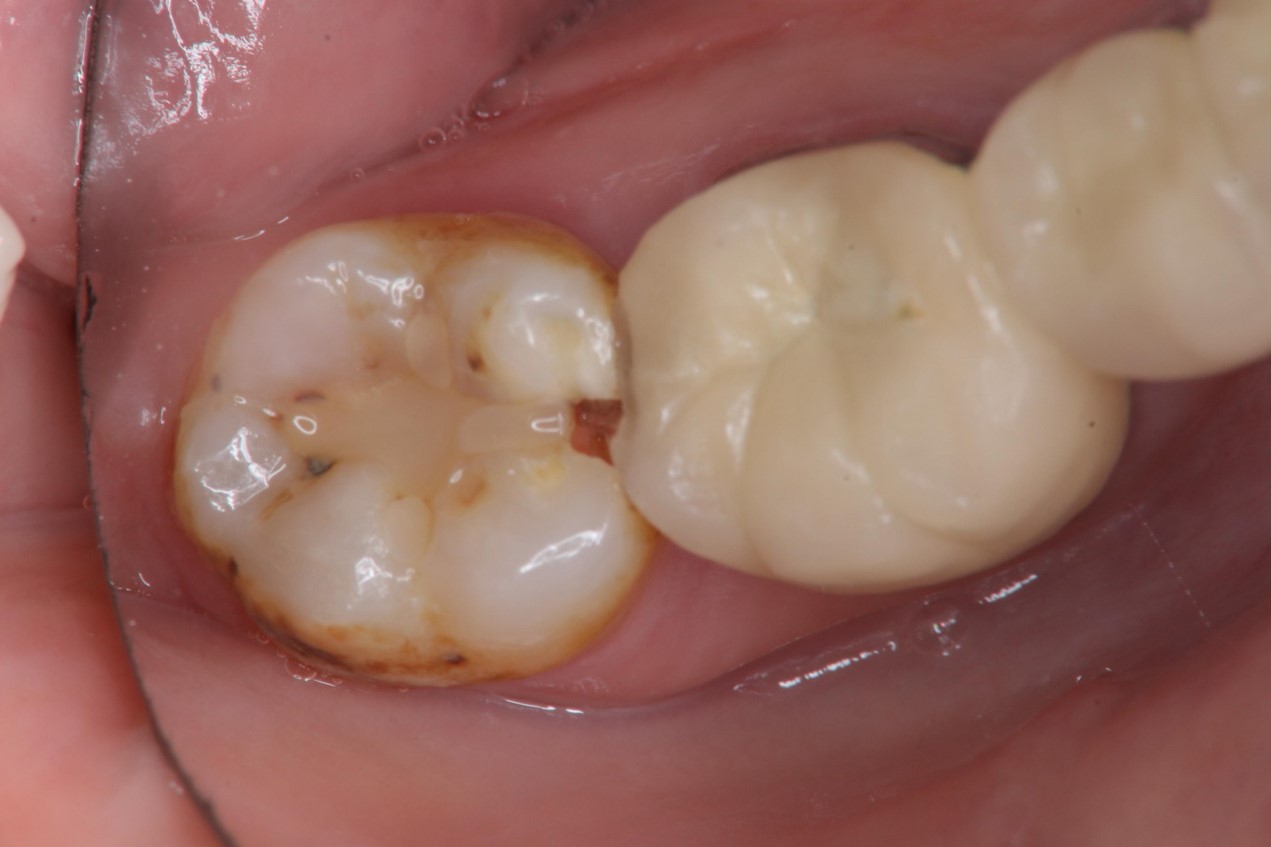

治療前,右下顎第二大臼齒二次蛀牙

右下顎第二大臼齒二次蛀牙